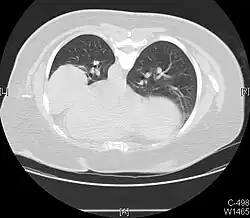

Atelectasis

Atelectasis is the partial collapse of a lung that is reversible. There are numerous etiologies, including post-operative atelectasis, surfactant deficiency, mucus plugging, and foreign body aspiration. Notably, post-operative atelectasis is thought to be caused by general anesthesia administration. Collapse of the affected lung shifts mediastinal structure towards the same side and can be observed on chest x-ray or CT. Radiographic features include increased opacification of collapsed lung and/or tracheal shift.[14]